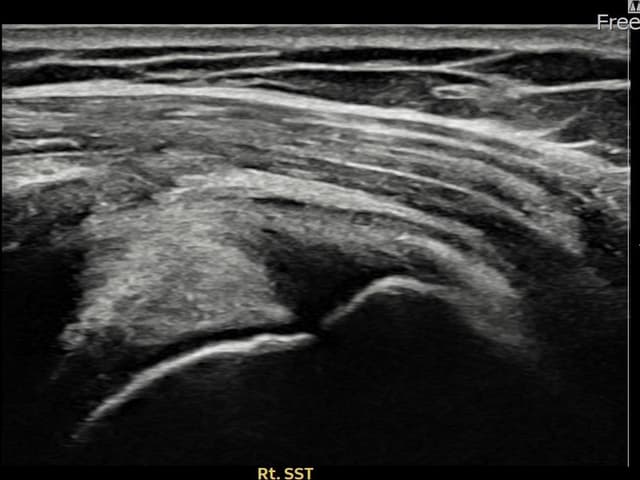

治療実績 — 超音波エビデンス

実際の患者様の施術前後の超音波画像。

手術なしで実現できる回復をご確認ください。

すべての超音波画像は患者様の同意を得て掲載しています。個人差があり、同一の結果を保証するものではありません。

[経過期間: 24.04.26~24.07.05]

[縫縮術] 超音波検査にて右 棘上筋腱 관절면측 광범위 部分断裂(16mm × 5mm (腱厚の約75%欠損))を確認。縫縮術施行後、腱の連続性が回復し、日常生活に復帰されました。